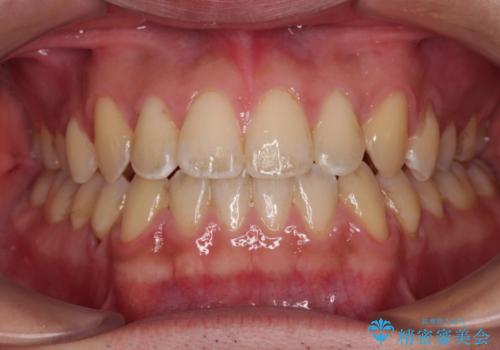

上下前歯が接触しない オープンバイトをインビザラインで改善

- 前歯の上下スペースによる食べにくさを気にして来院された患者様です。

インビザラインにより上下の前歯の隙間を閉じていくこととしました。

上下の奥歯を圧下させるようにすることで、前歯を接触させるように計画しました。

上下の隙間に舌が入り込むことがオープンバイトの原因であったため、舌の筋肉のトレーニングも並行して行い、後戻りの抑制を図りました。